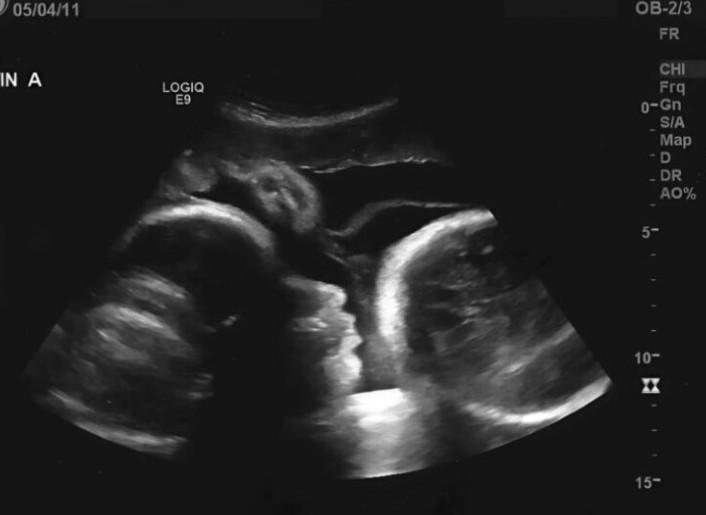

Guardando lo schermo dell’ecografia, il volto del dottore impallidì all’improvviso, e con voce tremante rivelò la dolorosa verità. Larisa non era incinta: i primi esami avevano dato un risultato fuorviante. Il gonfiore del suo addome non era causato da un bambino in crescita, ma da un enorme tumore ovarico che stava consumando il suo corpo dall’interno.

Le parole del medico furono devastanti per Larisa. La sensazione di “movimento” che percepiva era in realtà dovuta alla pressione del tumore sui suoi organi. Inoltre, avendo rimandato così a lungo le cure mediche, le cellule cancerose si erano già diffuse nel suo corpo. Il medico le disse con crudezza: “Se fosse venuta subito, avremmo potuto salvarla, ma ora la situazione è estremamente critica.”